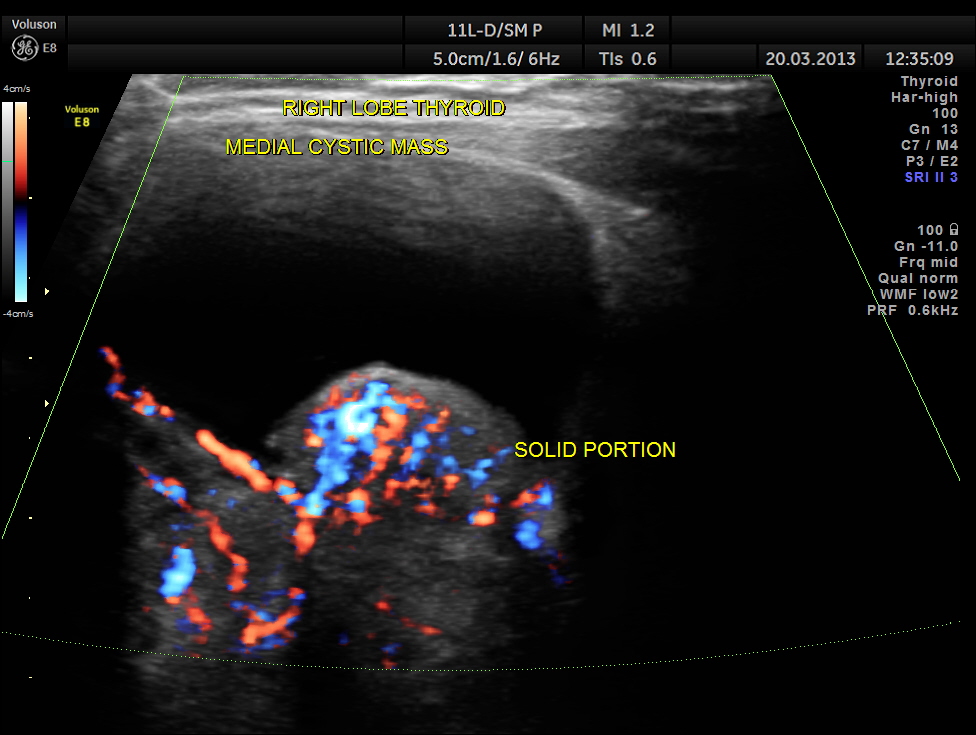

The right lobe of the thyroid was grossly enlarged , with predominantly cystic appearance , with eccentric solid tissue, with prominently increased vascularity in the solid portion.